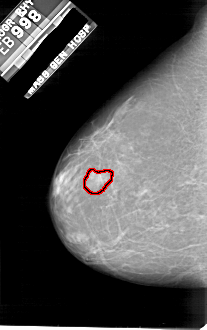

A_1811_1.LEFT_CC

LEFT_CC LINES 4936 PIXELS_PER_LINE 3091 BITS_PER_PIXEL 12 RESOLUTION 43.5 OVERLAY

FILE: A_1811_1.LEFT_CC.OVERLAY

TOTAL_ABNORMALITIES 1

ABNORMALITY 1

LESION_TYPE MASS SHAPE IRREGULAR MARGINS MICROLOBULATED

ASSESSMENT 4

SUBTLETY 2

PATHOLOGY BENIGN

TOTAL_OUTLINES 1

BOUNDARY